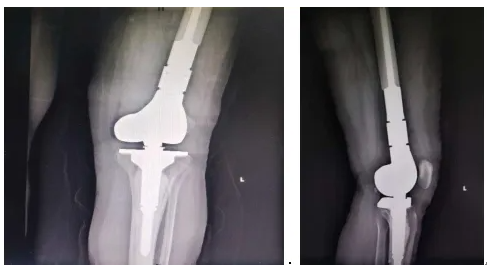

术后患者CT图。图源 重庆大学附属黔江医院